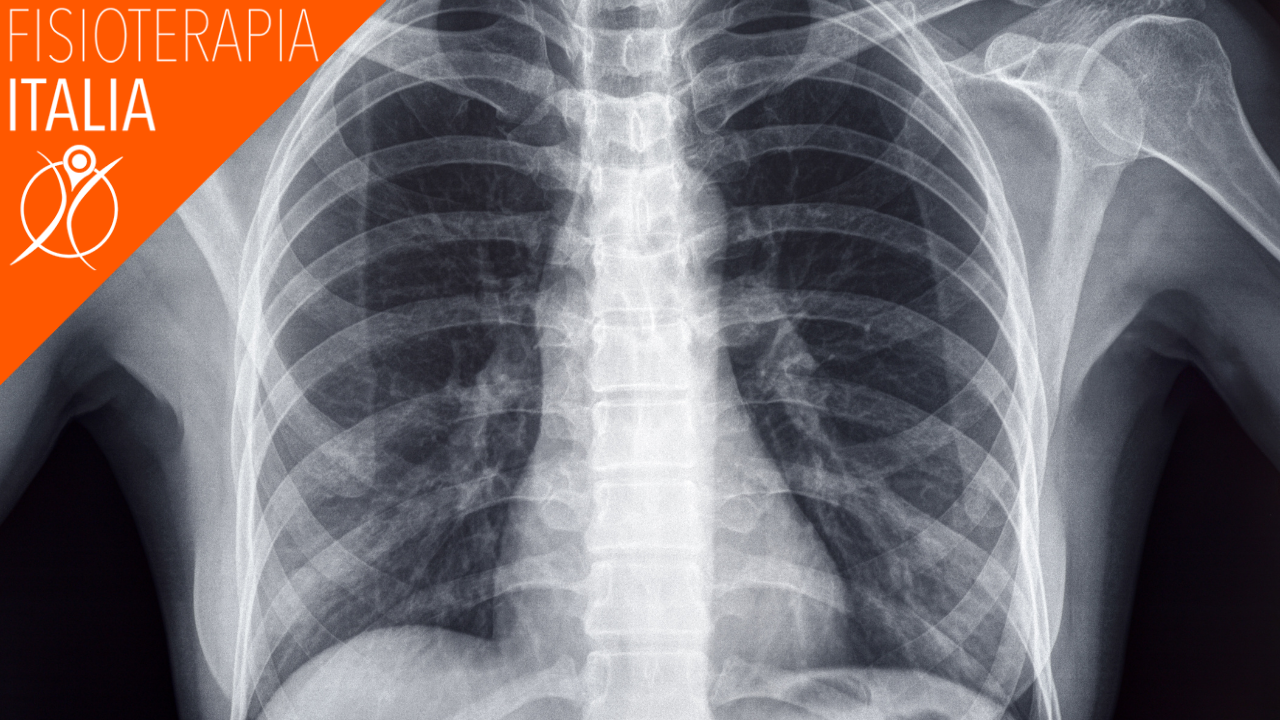

I dolori intercostali sono dolori che colpiscono la gabbia toracica. La gabbia toracica è una struttura cava che contiene importanti organi come il cuore, i polmoni e l’esofago. I dolori intercostali possono essere provocati da una moltitudine di fattori, più o meno gravi.

Quando si esaminano le potenziali cause e il modo in cui valutare un dolore intercostale è utile conoscere le strutture all'interno e intorno alla gabbia toracica.

Le coste, insieme allo sterno e alla colonna dorsale, costituiscono la gabbia toracica: una vera e proprio “gabbia” all’interno della quale sono contenute le più importanti strutture anatomiche del nostro organismo, come il cuore e i polmoni.